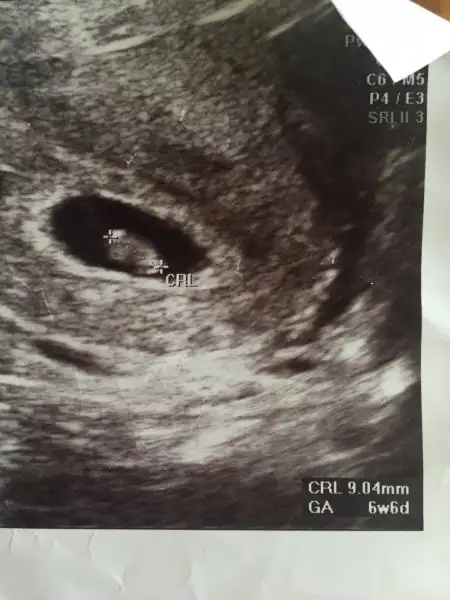

Merhaba bir de bunu yorumlayabilir misiniz plesanta yönüne göre 6 hafta 4 günlükUltrason vajinalse erkek abdominalse kız gibi

kızMerhaba bir de bunu yorumlayabilir misiniz plesanta yönüne göre 6 hafta 4 günlük

Vajinalse erkek gibi abdominalse kiz gibiMerhaba bir de bunu yorumlayabilir misiniz plesanta yönüne göre 6 hafta 4 günlük